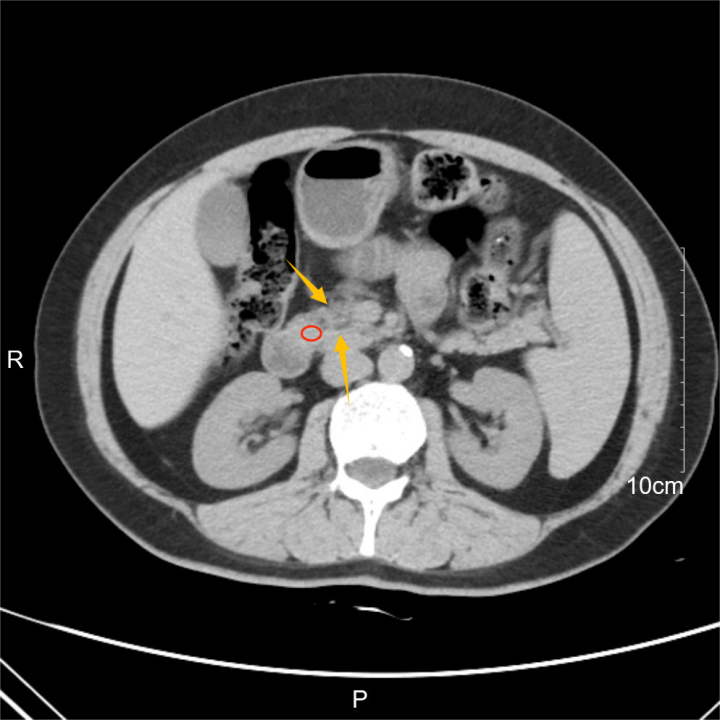

改寫手術(shù)史!多家三甲不敢收,西京教授自創(chuàng)術(shù)式突破手術(shù)禁區(qū)原創(chuàng)?丁香園DXY?丁香園?2025年02月10日12:24?浙江?73人本文作者:ZJUN2024年12月9日,65歲的患者終于如愿被推進(jìn)空軍軍醫(yī)大學(xué)第一附屬醫(yī)院(西京醫(yī)院)的手術(shù)室。為了這個(gè)手術(shù),她去往多家三甲醫(yī)院,但很多醫(yī)院表示對(duì)手術(shù)成功的把握性不大。因?yàn)樗且晃痪植客砥谝认侔┗颊摺T趧倓偞_診時(shí),她的腫瘤就已經(jīng)被各大指南宣判為「不可切除」。發(fā)現(xiàn)即晚期,「不可切除」的腫瘤非切不可2024年末,65歲的王麗(化名)出現(xiàn)了上腹部不適的癥狀,起初她并未太在意,只當(dāng)是平常的胃部不適,以為休息幾天就會(huì)好轉(zhuǎn)。但隨著時(shí)間的推移,這種不適并沒有緩解,反而還有加重的趨勢。隨后,她決定在當(dāng)?shù)蒯t(yī)院就診,此時(shí)距離王麗出現(xiàn)癥狀僅過去了10天。經(jīng)過腹部CT檢查發(fā)現(xiàn),她的胰頭部出現(xiàn)了一個(gè)腫物占位,這個(gè)腫物將周圍許多血管緊緊地包裹在里面。后來穿刺活檢也證實(shí)了,王麗得的是胰腺癌,并且腫瘤已經(jīng)包繞了腹腔干和腸系膜上動(dòng)脈達(dá)到了360度。換句話講,這已經(jīng)屬于局部晚期胰腺癌。圖源:治療團(tuán)隊(duì)提供2024年中國抗癌協(xié)會(huì)(CACA)發(fā)布的中國腫瘤整合診治指南明確指出,「根治性(R0)切除是目前治療胰腺癌最有效的方法?!筟1]但同時(shí)指南也規(guī)定,胰頭和胰頸部腫瘤觸及腸系膜上動(dòng)脈超過180度,腫瘤侵犯腹腔干超過180度,被定義為「不可切除」,這種情況的胰腺癌也被稱為「外科手術(shù)的禁區(qū)」。圖源:參考資料1根據(jù)2023版美國NCCN指南,如果局部進(jìn)展期胰腺癌患者不接受手術(shù),預(yù)后極差,中位生存期通常在6~12個(gè)月。[2]這也意味著,如果不手術(shù),王麗的預(yù)后很不樂觀,只有切除腫瘤,才能控制病情進(jìn)一步惡化。這個(gè)「不可切除」的腫瘤,非切不可。隨即王麗在家人的陪伴下,趕緊去往北京的大醫(yī)院尋求進(jìn)一步治療。目前國內(nèi)外各大權(quán)威指南認(rèn)為,對(duì)于局部進(jìn)展期胰腺癌的治療,初始治療均不推薦手術(shù)。并且患者的腫瘤位置非常特殊,一旦損傷血管,等待患者的可能是不止一個(gè)器官的缺血壞死。為了這個(gè)手術(shù),她去往多家三甲醫(yī)院,但很多表示對(duì)手術(shù)成功的把握性不大。多家醫(yī)院的專家給出的治療方案和指南給出治療方案基本一致,先輔助化療,待腫瘤體積縮小后再考慮手術(shù)切除。但術(shù)前的化療也不是絕對(duì)有效,專家告知王麗,胰腺癌對(duì)化療并不敏感,術(shù)前輔助化療有效率僅有30%左右,一旦化療失敗,還有可能出現(xiàn)腫瘤惡化甚至遠(yuǎn)處轉(zhuǎn)移的可能。以王麗目前的病情,她已經(jīng)沒有試錯(cuò)的余地了,化療的時(shí)間她等不起,化療的不確定性她也承受不起,現(xiàn)在的當(dāng)務(wù)之急就是盡快切掉腫瘤。于是,王麗又輾轉(zhuǎn)了多家大三甲醫(yī)院,得到的都是類似的回答。沒有哪家醫(yī)院有把握能直接手術(shù)切除腫瘤,畢竟風(fēng)險(xiǎn)太大,超越指南推薦的手術(shù),出現(xiàn)了問題的后果醫(yī)生和患者都難以承擔(dān)。就在走投無路之際,患者家屬認(rèn)識(shí)的一位權(quán)威專家突然想到一個(gè)人,就在一個(gè)多月前,西京醫(yī)院的楊雁靈教授團(tuán)隊(duì)為一位來自東北的53歲原位晚期胰腺癌患者進(jìn)行了手術(shù)治療,自體小腸移植聯(lián)合胰十二指腸切除,術(shù)后的效果很理想,患者已順利康復(fù)出院。于是這位專家建議她去找楊雁靈教授就診咨詢,或許他那里會(huì)有王麗想要的解決辦法。既然沒有參考,干脆自創(chuàng)「西京術(shù)式」家屬立刻帶著所有檢查結(jié)果來到西京醫(yī)院楊雁靈教授的門診。楊雁靈教授此前也為多例局部進(jìn)展期胰腺癌患者進(jìn)行過手術(shù),對(duì)這種「不可切除」的腫瘤有著豐富的臨床經(jīng)驗(yàn)。在初步看過王麗的檢查結(jié)果后,楊雁靈教授認(rèn)為患者還有手術(shù)切除的可能。隨后,在經(jīng)過患者和家屬的認(rèn)真討論后,王麗住進(jìn)了西京醫(yī)院肝膽外科的病房。但對(duì)于局部進(jìn)展期胰腺癌的病人,指南并不推薦手術(shù)為首選治療方案,王麗的病情也十分特殊,既往沒有完全相同的病例或者手術(shù)圖鑒可以參考。手術(shù)怎么做?成了新的問題。隨即在患者入院后,肝膽外科的竇科峰院士組織了全科室的討論會(huì)。楊雁靈教授表示,患者胰腺占位不僅僅包繞著腹腔干和腸系膜上動(dòng)脈,肝總動(dòng)脈和脾動(dòng)靜脈也有不同程度的受累。腹腔干和腸系膜上動(dòng)脈,這兩根血管供應(yīng)腹腔內(nèi)所有重要臟器血供。若按照傳統(tǒng)手術(shù)方式直接切除腫瘤可能導(dǎo)致大出血、肝衰竭、全胃腸壞死等嚴(yán)重并發(fā)癥。如果單純把腫瘤從血管剝除,達(dá)不到根治,腫瘤會(huì)復(fù)發(fā)、生長、轉(zhuǎn)移,生存周期也會(huì)縮短。若采用姑息療法,利用胃和腸「架橋」,雖可以解決吃飯難題,但腫瘤依然存在。楊雁靈教授很快在文獻(xiàn)庫中檢索出以前看到的一例國外類似的特殊病例報(bào)道。一位7歲的女孩因肌纖維母細(xì)胞瘤,累及腹腔動(dòng)脈和腸系膜上動(dòng)脈。由于其位置特殊,該腫瘤無法通過常規(guī)手術(shù)方法切除。圖源:參考資料3治療團(tuán)隊(duì)采取了一種創(chuàng)新的手術(shù)方式——離體腫瘤切除聯(lián)合自體移植術(shù),通俗來講,就是把胰、胃、脾、肝、小腸等全腹腔臟器全部切除離體,進(jìn)行體外灌注,完全暴露腹腔的腫瘤并完整切除后,只留下肝臟和部分小腸進(jìn)行自體移植。離體手術(shù)技術(shù)在確保內(nèi)臟器官完整保留的同時(shí)可以完全暴露腹腔干和腸系膜血管根部,因此為腫瘤完整切除、主要血管重建、減少末梢器官缺血損傷提供了可能。此外,成功的自體移植技術(shù)還會(huì)降低異體移植的必要性,進(jìn)而減少異體移植并發(fā)癥的發(fā)生。但話又說回來,全腹腔臟器離體灌注、切除腫瘤再多臟器自體移植,手術(shù)工程龐大、操作細(xì)節(jié)繁瑣,每個(gè)器官離體的時(shí)間都有限制,且術(shù)后并發(fā)癥風(fēng)險(xiǎn)極大,不確定因素太多。腫瘤一定要切,但有沒有一種創(chuàng)傷既沒那么大,又能將腫瘤完整切除的手術(shù)方案呢?這個(gè)方案還真被楊雁靈教授找到了。經(jīng)過詳細(xì)的術(shù)前討論和多學(xué)科會(huì)診,憑借治療團(tuán)隊(duì)長期從事肝移植的經(jīng)驗(yàn)和掌握血管重建吻合的熟練技術(shù)??剖矣懻摵笞罱K做出了決定。既然沒有參考,干脆自創(chuàng)一個(gè)屬于西京醫(yī)院的全新的術(shù)式。手術(shù)在保留離體手術(shù)切除范圍的基礎(chǔ)上,優(yōu)先建立肝臟和小腸的動(dòng)脈血流,這一步的目的是保證重要臟器血供和為后續(xù)的自體小腸移植做準(zhǔn)備,重建重要血管后,就可以避免自體臟器移植的缺血再灌注損傷、高鉀等并發(fā)癥,同時(shí)也可保證有充足的時(shí)間切除腫瘤。楊雁靈教授主持術(shù)前討論圖源:治療團(tuán)隊(duì)提供這一步改寫手術(shù)史手術(shù)的方案基本已經(jīng)確定了,下一步就是做好萬全的打算,準(zhǔn)備實(shí)施。2024年12月9日,在經(jīng)過詳盡的術(shù)前準(zhǔn)備后,王麗被推進(jìn)了手術(shù)室。這場「沒有參考」的手術(shù),由楊雁靈教授主刀。術(shù)中,楊雁靈教授先正中繞臍做切口,逐層分離組織暴露腹腔,在探查無轉(zhuǎn)移擴(kuò)散后,顯露游離腹主動(dòng)脈、肝總動(dòng)脈、腸系膜上動(dòng)脈。接下來就是進(jìn)行本次手術(shù)創(chuàng)新的一步——腹主動(dòng)脈人工血管架橋、優(yōu)先重建肝臟和小腸的血供,這也是以往外科術(shù)式中都沒有的一步。腹主動(dòng)脈人工血管架橋示意圖(西京術(shù)式)圖源:治療團(tuán)隊(duì)提供為了確保肝臟和小腸的血供,需要在安全時(shí)限內(nèi)完成肝臟和小腸等重要臟器的血管阻斷和重建,這個(gè)過程要建立3個(gè)吻合口。第一個(gè)吻合口在左腎靜脈下方,需要在腹主動(dòng)脈前壁打孔與人工血管的端側(cè)吻合,第二個(gè)吻合口是在人工血管中段打孔,與腸系膜上動(dòng)脈的遠(yuǎn)端行端側(cè)吻合,第三個(gè)吻合口則是人工血管遠(yuǎn)端,與肝總動(dòng)脈行端端吻合。每一個(gè)吻合口都需要在10分鐘之內(nèi)完成。圖源:治療團(tuán)隊(duì)提供完成吻合后意味著重要臟器動(dòng)脈血流得以重建,此時(shí),楊雁靈教授發(fā)現(xiàn),王麗的腹腔干和主要分支因受腫瘤太多侵蝕,已無法重建,于是他當(dāng)即決定行腹腔干供血區(qū)域的聯(lián)合臟器切除,即全胰切除(包括胰頭十二指腸、胰體尾聯(lián)合腹腔干和腸系膜上動(dòng)脈起始部切除)聯(lián)合全胃、脾切除術(shù)。楊雁靈教授表示,從外科和解剖學(xué)角度,部分切除胰腺很難做到將腫瘤完全切除干凈,而全胰切除則不存在這個(gè)問題,同時(shí),全胰切除無需作胰腸吻合,術(shù)后也不會(huì)發(fā)生胰瘺等嚴(yán)重并發(fā)癥。很快,包裹著腹腔干和腸系膜上動(dòng)脈的瘤體被切了下來,一同切下來的還有瘤體周圍的組織,切下來的標(biāo)本立刻被送往病理科做冰凍檢查。與此同時(shí),臺(tái)上的手術(shù)也在有條不紊的進(jìn)行著。瘤體中的腹腔干和腸系膜上動(dòng)脈(SMA)圖源:治療團(tuán)隊(duì)提供就在這時(shí),冰凍的結(jié)果也回報(bào)切緣均為陰性,這也意味著腫瘤被切除得很完整,沒有任何殘留。隨后治療團(tuán)隊(duì)又為王麗實(shí)施了包括膽腸吻合、食管空腸吻合、腸腸吻合等步驟在內(nèi)的消化道重建術(shù)。終于,在王麗被推進(jìn)手術(shù)室的8個(gè)小時(shí)以后,手術(shù)結(jié)束了。術(shù)后王麗被送往ICU觀察1天,病情平穩(wěn)后,她轉(zhuǎn)回了普通病房。術(shù)后楊雁靈教授團(tuán)隊(duì)給予患者抗凝、營養(yǎng)支持、調(diào)控血糖等基本治療,同時(shí),患者每天需要進(jìn)行超聲檢查腸系膜血管、肝動(dòng)脈和門靜脈血流,以確保吻合的血管通暢。令人欣慰的是,王麗術(shù)后恢復(fù)得非常好,沒有出現(xiàn)任何的并發(fā)癥,在術(shù)后的第3天,王麗就可以開始經(jīng)口進(jìn)流食了,目前,王麗已經(jīng)順利出院,回家繼續(xù)康復(fù),準(zhǔn)備在當(dāng)?shù)蒯t(yī)院進(jìn)行術(shù)后化療等綜合治療。圖源:治療團(tuán)隊(duì)提供致謝:本文經(jīng)??空軍軍醫(yī)大學(xué)西京醫(yī)院肝膽外科主任醫(yī)師?楊雁靈?專業(yè)審核空軍軍醫(yī)大學(xué)西京醫(yī)院肝膽外科楊雁靈教授?審核意見胰十二指切除術(shù)號(hào)稱普外科難度最大的手術(shù),自體小腸移植也是超高難度的手術(shù)。自體小腸移植聯(lián)合胰十二指切除是普外科絕對(duì)的頂級(jí)手術(shù)。全球也不過開展數(shù)十例,手術(shù)風(fēng)險(xiǎn)極大,據(jù)梅奧統(tǒng)計(jì),術(shù)后胰瘺的風(fēng)險(xiǎn)可達(dá)80%,故鮮有醫(yī)生嘗試。此例手術(shù)的創(chuàng)新之處,腹主動(dòng)脈人工血管架橋,先建立肝臟和小腸的動(dòng)脈血流(免灌注的自體小腸移植),然后再切除腫瘤。避免了自體臟器移植的缺血再灌注損傷、高鉀等弊端。?該手術(shù)沒有類似報(bào)道、沒有圖譜、沒有文獻(xiàn)參考可依,還突破外科指南。該手術(shù)方式為西京醫(yī)院原創(chuàng)術(shù)式,也被業(yè)內(nèi)同行譽(yù)為「西京術(shù)式」。為什么每年都要頒布最新的胰腺癌治療指南,因?yàn)橛懈矣趧?chuàng)新的專家學(xué)者在不停地嘗試和更新更佳的治療措施,獲得同行和患者的認(rèn)可和支持,推動(dòng)醫(yī)學(xué)不斷進(jìn)步。策劃:ZJUN|監(jiān)制:islay題圖來源:治療團(tuán)隊(duì)提供參考資料:[1]2024?中國腫瘤整合診治指南(CACA)——胰腺癌[2]NCCNGuidelinesVersion2.2023PancreaticAdenocarcinoma.[3]https://doi.org/10.1111/j.1600-6143.2011.03945.x丁香園是面向醫(yī)療從業(yè)者的專業(yè)平臺(tái),以「助力中國醫(yī)生」為己任。在丁香園,可以和同行討論病例,在線學(xué)習(xí)公開課,使用用藥助手等臨床決策工具,在丁香人才找可靠醫(yī)療崗位。丁香園千萬醫(yī)務(wù)工作者的網(wǎng)上家園。我們深知醫(yī)療的痛苦與快樂,在丁香園里,您可以了解最新資訊、閱讀深度報(bào)道,并與同行進(jìn)行交流。4198篇原創(chuàng)內(nèi)容公眾號(hào)閱讀?8.7萬?

突破禁區(qū)!新術(shù)式根治切除進(jìn)展期胰腺癌西京醫(yī)院?2025年02月07日07:02?陜西胰腺癌發(fā)病率呈持續(xù)上升態(tài)勢,作為預(yù)后極差的消化道腫瘤,具有早期診斷困難、手術(shù)切除率低、術(shù)后并發(fā)癥多等特點(diǎn)。在最新國內(nèi)和國際胰腺癌治療指南中,局部進(jìn)展期胰腺癌,腫瘤侵犯腸系膜上動(dòng)脈(SMA)超過180度、或侵犯腹腔干動(dòng)脈(CA)超過180度,界定為不可切除的胰腺癌,即局部晚期胰腺癌。指南建議先化療、瘤體縮小后再手術(shù),然而胰腺癌化療有效率常不到30%,一旦化療無效可能面臨腫瘤擴(kuò)散轉(zhuǎn)移等嚴(yán)重后果。面對(duì)進(jìn)展期胰腺癌治療難題,特別是其侵犯重要血管導(dǎo)致的不可切除性,西京醫(yī)院肝膽外科楊雁靈教授團(tuán)隊(duì)采用自體小腸移植和重要臟器血管優(yōu)先重建等新技術(shù),于日前為兩名進(jìn)展期胰腺癌患者實(shí)施根治性手術(shù)切除,并取得良好治療效果。胰腺胰頭部位異常占位包繞腸系膜上動(dòng)脈自體小腸移植聯(lián)合胰十二指腸、右半結(jié)腸切除53歲的患者李忠(化名)檢查發(fā)現(xiàn)胰腺胰頭部位出現(xiàn)異常增生(胰頭占位)并且增生組織包繞腸系膜上動(dòng)脈(SMA),通常長在這個(gè)地方的腫瘤,被稱為“外科手術(shù)禁區(qū)”:腸系膜上動(dòng)脈血液供應(yīng)小腸和右半部分結(jié)腸,直接切除腫瘤,小腸會(huì)缺血壞死,完全喪失營養(yǎng)吸收能力。如果單純把腫瘤從血管剝除,達(dá)不到根治,腫瘤會(huì)復(fù)發(fā)、生長、轉(zhuǎn)移,生存周期也會(huì)縮短。若采用姑息療法,利用胃和腸“架橋”,可以解決吃飯難題,但腫瘤依然存在。李忠輾轉(zhuǎn)多地求醫(yī),均建議先行化療,待瘤體縮小后再考慮手術(shù)。面對(duì)這一困境,與家人經(jīng)過深思熟慮,決定尋求手術(shù)根治機(jī)會(huì)。然而,多家醫(yī)院均表示手術(shù)難度極大,沒有完全把握。經(jīng)多方打聽后,來到西京醫(yī)院肝膽外科,在細(xì)致檢查后,竇科峰院士組織進(jìn)行多次討論,決定實(shí)施自體小腸移植。然而,自體小腸移植面臨眾多風(fēng)險(xiǎn)難關(guān):小腸血管豐富、分叉眾多,移植過程中稍有不慎就可能形成血栓或血管無法對(duì)接,引發(fā)腸壞死、大出血。此外,胰十二指腸腫瘤切除后需重建消化道,涉及4個(gè)吻合口,一旦發(fā)生吻合口瘺,感染將難以控制,即使移植手術(shù)成功也可能功虧一簣。經(jīng)過充分的術(shù)前準(zhǔn)備后,肝膽外科楊雁靈教授主刀,實(shí)施自體小腸移植聯(lián)合胰十二指腸切除、右半結(jié)腸切除。術(shù)中,通過正中切口進(jìn)入腹腔,仔細(xì)游離胰頭、小腸及升結(jié)腸,并對(duì)受侵的腸系膜上動(dòng)靜脈進(jìn)行骨骼化處理,使其清晰可辨。之后,在腫瘤遠(yuǎn)端離斷腸系膜上動(dòng)靜脈并取下小腸,通過腸系膜上動(dòng)脈斷端充分灌注小腸,以確保其活力。在灌注的同時(shí),精準(zhǔn)切除腫瘤,同時(shí)完成胰十二指腸切除和右半結(jié)腸切除。與此同時(shí),對(duì)腸系膜根部血管進(jìn)行細(xì)致修整,為接下來的小腸回植做好充分準(zhǔn)備,將小腸回植原位,進(jìn)行腸系膜上動(dòng)靜脈端端吻合,血流恢復(fù)后,小腸狀態(tài)良好。其后,手術(shù)團(tuán)隊(duì)又精心完成胰腸、膽腸、胃腸吻合,重建消化道。每個(gè)吻合口都至關(guān)重要,任何細(xì)微滲漏都可能導(dǎo)致手術(shù)失敗。歷經(jīng)近9小時(shí),手術(shù)終獲成功。對(duì)移植患者來說,手術(shù)成功僅僅是第一步,術(shù)后護(hù)理同樣面臨諸多挑戰(zhàn)。治療團(tuán)隊(duì)每日查房3-4次,密切關(guān)注各項(xiàng)指標(biāo),根據(jù)實(shí)際情況及時(shí)調(diào)整治療方案。術(shù)后病理確定胰腺癌,并獲得腫瘤基因突變位點(diǎn)關(guān)鍵信息。根據(jù)疾病特點(diǎn),醫(yī)療團(tuán)隊(duì)制定綜合術(shù)后治療措施?;颊呋謴?fù)順利,術(shù)后4周出院,正常進(jìn)食,現(xiàn)已結(jié)束首次化療返回家中。?胰腺占位包繞腹腔干和腸系膜上動(dòng)脈,重要臟器血管優(yōu)先重建?自體小腸移植聯(lián)合全胰、全胃及脾切除一名患者王麗(化名)65歲,因上腹部不適,在腹部CT時(shí)顯示胰腺占位包繞腹腔干和腸系膜上動(dòng)脈(360度侵犯),兩根血管供應(yīng)腹腔內(nèi)所有重要臟器血供,強(qiáng)行切除可能導(dǎo)致大出血、肝衰竭、全胃腸壞死等嚴(yán)重并發(fā)癥。國外有類似病例報(bào)道,手術(shù)采用全腹腔臟器切除離體,體外灌注切除腫瘤,后進(jìn)行自體肝移植和自體小腸移植,手術(shù)工程龐大、操作細(xì)節(jié)繁瑣且術(shù)后風(fēng)險(xiǎn)極大,敢于嘗試的醫(yī)院寥寥無幾。為尋求更佳的治療方案,王麗又進(jìn)一步做穿刺活檢,結(jié)果疑似胰腺癌,在多家醫(yī)院就診,均無法切除、建議化療。來到西京醫(yī)院肝膽外科,經(jīng)科室反復(fù)討論后,決定實(shí)施自體小腸移植聯(lián)合全胰切除、全胃及脾切除術(shù)。術(shù)中,楊雁靈教授手術(shù)團(tuán)隊(duì)巧妙應(yīng)用腹主動(dòng)脈人工血管架橋技術(shù),優(yōu)先重建重要臟器動(dòng)脈,再切除腫瘤,在安全時(shí)限內(nèi)完成肝臟和小腸等重要臟器的血管阻斷和重建,每個(gè)吻合口處理時(shí)間均控制在10分鐘以內(nèi),為接下來的自體小腸移植奠定堅(jiān)實(shí)基礎(chǔ),實(shí)現(xiàn)了免灌注移植,有效避免了缺血再灌注損傷和高血鉀等潛在風(fēng)險(xiǎn)。在重要臟器動(dòng)脈血流得以重建后,手術(shù)團(tuán)隊(duì)從容不迫展開腫瘤切除。全胰切除、胃脾切除、腹腔干和SMA起始部切除等系列操作依次進(jìn)行,同時(shí),冰凍結(jié)果顯示切緣陰性,表示腫瘤被徹底切除。隨后,又進(jìn)行消化道重建,包括膽腸吻合、食管空腸吻合、腸腸吻合等步驟。該項(xiàng)手術(shù)沒有類似報(bào)道、圖譜或文獻(xiàn)參考可依,突破了外科指南常規(guī)框架,手術(shù)方式為原創(chuàng)術(shù)式。目前,患者恢復(fù)順利,已經(jīng)開始進(jìn)食,并順利出院。(作者:李偉民)https://mp.weixin.qq.com/s?__biz=MzU1NTAxMTc4Mw==&mid=2247508057&idx=1&sn=c8f4906541df9006b350262064dd0561&chksm=faa8e6c544c7caf96589441df1c7cad83cc311ad7264db7b22a992e75db2d58a85949a12d534&scene=27